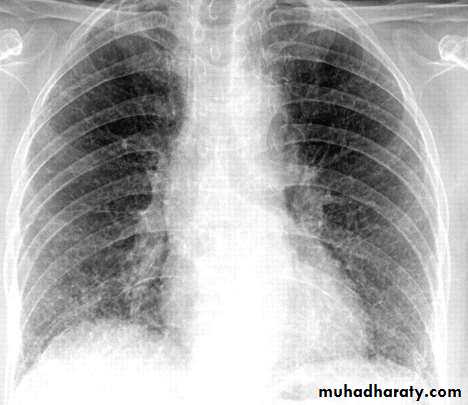

Chest X-ray and UltrasoundLobar pneumonia

• Patchy opacification ,consolidation.

• Air bronchogram (air-filled bronchi appear lucent against

consolidated lung tissue)

• X Ray

• Homogenous opacity with air bronchogram

• LOBAR PNEUMONIA

• Peripheral airspace consolidation pneumonia• Without prominent involvement of the bronchial tree

• RUL Consolidation

• RML Consolidation

• RLL Consolidation